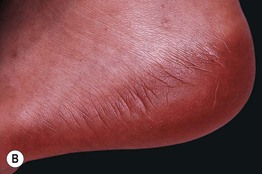

Fig. 17.14 Psoriasiform eruptions due to TNF-α inhibitors. A Widespread papulosquamous lesions in a patient being treated with infliximab for gastrointestinal GVHD. Histopathologically, there was no evidence of cutaneous GVHD. B Sterile pustulosis of the plantar surface developed in this patient with rheumatoid arthritis who had received infliximab for the previous 5 years. Neither patient had had a reduction in immunosuppression prior to the onset of the psoriasiform eruption. A, Courtesy, Dennis Cooper, MD. B, Courtesy, Chris Bunick, MD.